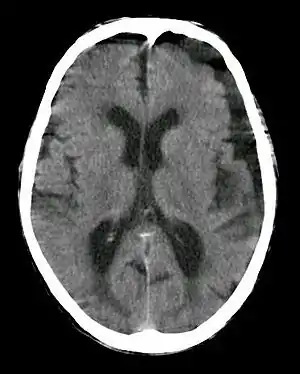

| Subdural hygroma, frontal and temporal. Man of 80 years old. | |